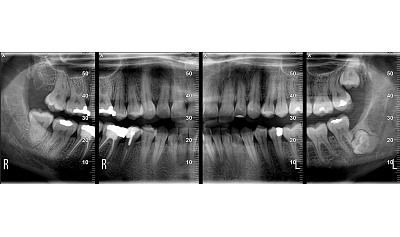

Diagnostinės galimybės

2D vaizdai

- Panoraminiai (PAN) vaizdai su keliais fokusavimo sluoksniais

- Cefalometriniai vaizdai (jei komplektacija su CEPH arm)

- Detalios žandikaulių sričių projekcijos

3D CBCT vaizdai

- SuperHD CBCT su MultiFOV funkcija nuo mažiausio (4x4) iki didžiausio (15x16) lauko

- Greitas 360° skenavimas ir mažos dozės protokolai

- Tiksli kaulinės struktūros diagnostika implantologijai, chirurgijai, ortodontijai ir ENT analizėms